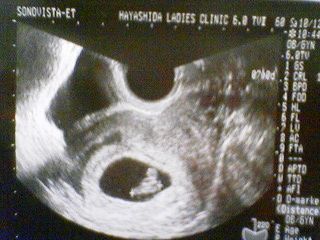

最近、めっきりサボりがちの、まりもです・・・実は、まりもに「赤ちゃん」ができました。で、昨日二度目の検診へ行ってきて、順調に成長してることが確認できたので、報告することにしました。まだ、7週目で大きさは「12mm」です。出産予定は、来年7月の末です。で、この2週間前位から、調子が悪く会社から帰っても、パソコンの前に座る気すらおきなくてぐったりしてました(~_~;)おなかがすくと気持ち悪くなるので、常に何か食べてます。会社でもいつも何かつまんでます・・・おかげで太ってきました・・・(-"-)まだ、おなかが出てくる時期ではないのに、なぜか(あきらかに食べすぎ!!)おなかが出てきて、服がきつくて大変です・・・とまあ、こんな感じで、しばらくはブログ更新なかなかできないかもしれませんが見捨てないでくださいね~\(-o-)/会社で皆さんのブログは拝見してますので、コメントは頑張って入れていきます(*^_^*)ご協力お願いします。↓HOMEへ